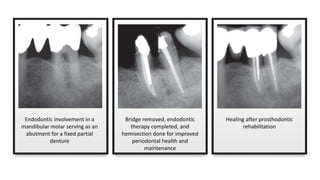

Endodontic involvement in a

mandibular molar serving as an

abutment for a fixed partial

Bridge removed, endodontic

therapy completed, and

hemisection done for improved

periodontal health and

maintenance

Healing after prosthodontic

rehabilitation